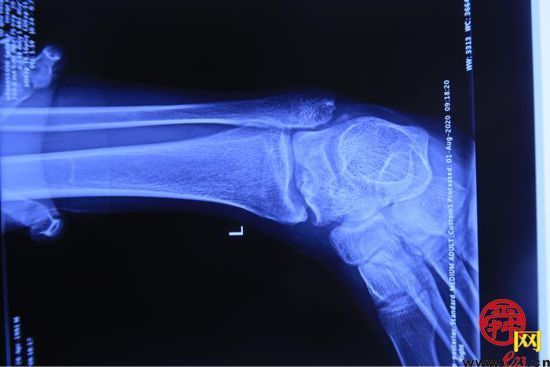

患者,男,28岁,左踝关节疼痛1年,加重3个月,影像学表现为左距骨内髁坏死、塌陷,面积约3*2cm大小。距骨坏死的治疗,对直径在2cm以内的距骨坏死,可以采用自体股骨髁骨软骨移植、自体带骨膜髂骨移植等方法,但对于直径超过2cm的距骨坏死,尤其是年轻患者,一直是治疗的难点。搜索国内外文献,对于超过2cm距骨坏死,一般采用踝关节融合、踝关节置换、同种异体距骨移植、全距骨置换等方法。但上述方法均有弊端:采用关节融合,患者丧失踝关节功能;踝关节置换、全距骨置换对于年轻、距骨单髁坏死患者,创伤大,且需要多次的返修手术;国外有采用同种异体新鲜距骨移植的报道,但目前国内还没有相关的骨组织工程库。经手术团队术前充分讨论,认为3D打印技术因其个性化的设计已经越来越多地应用于临床,决定对患者行3D打印距骨部分置换手术。

(术前患者的影像情况)